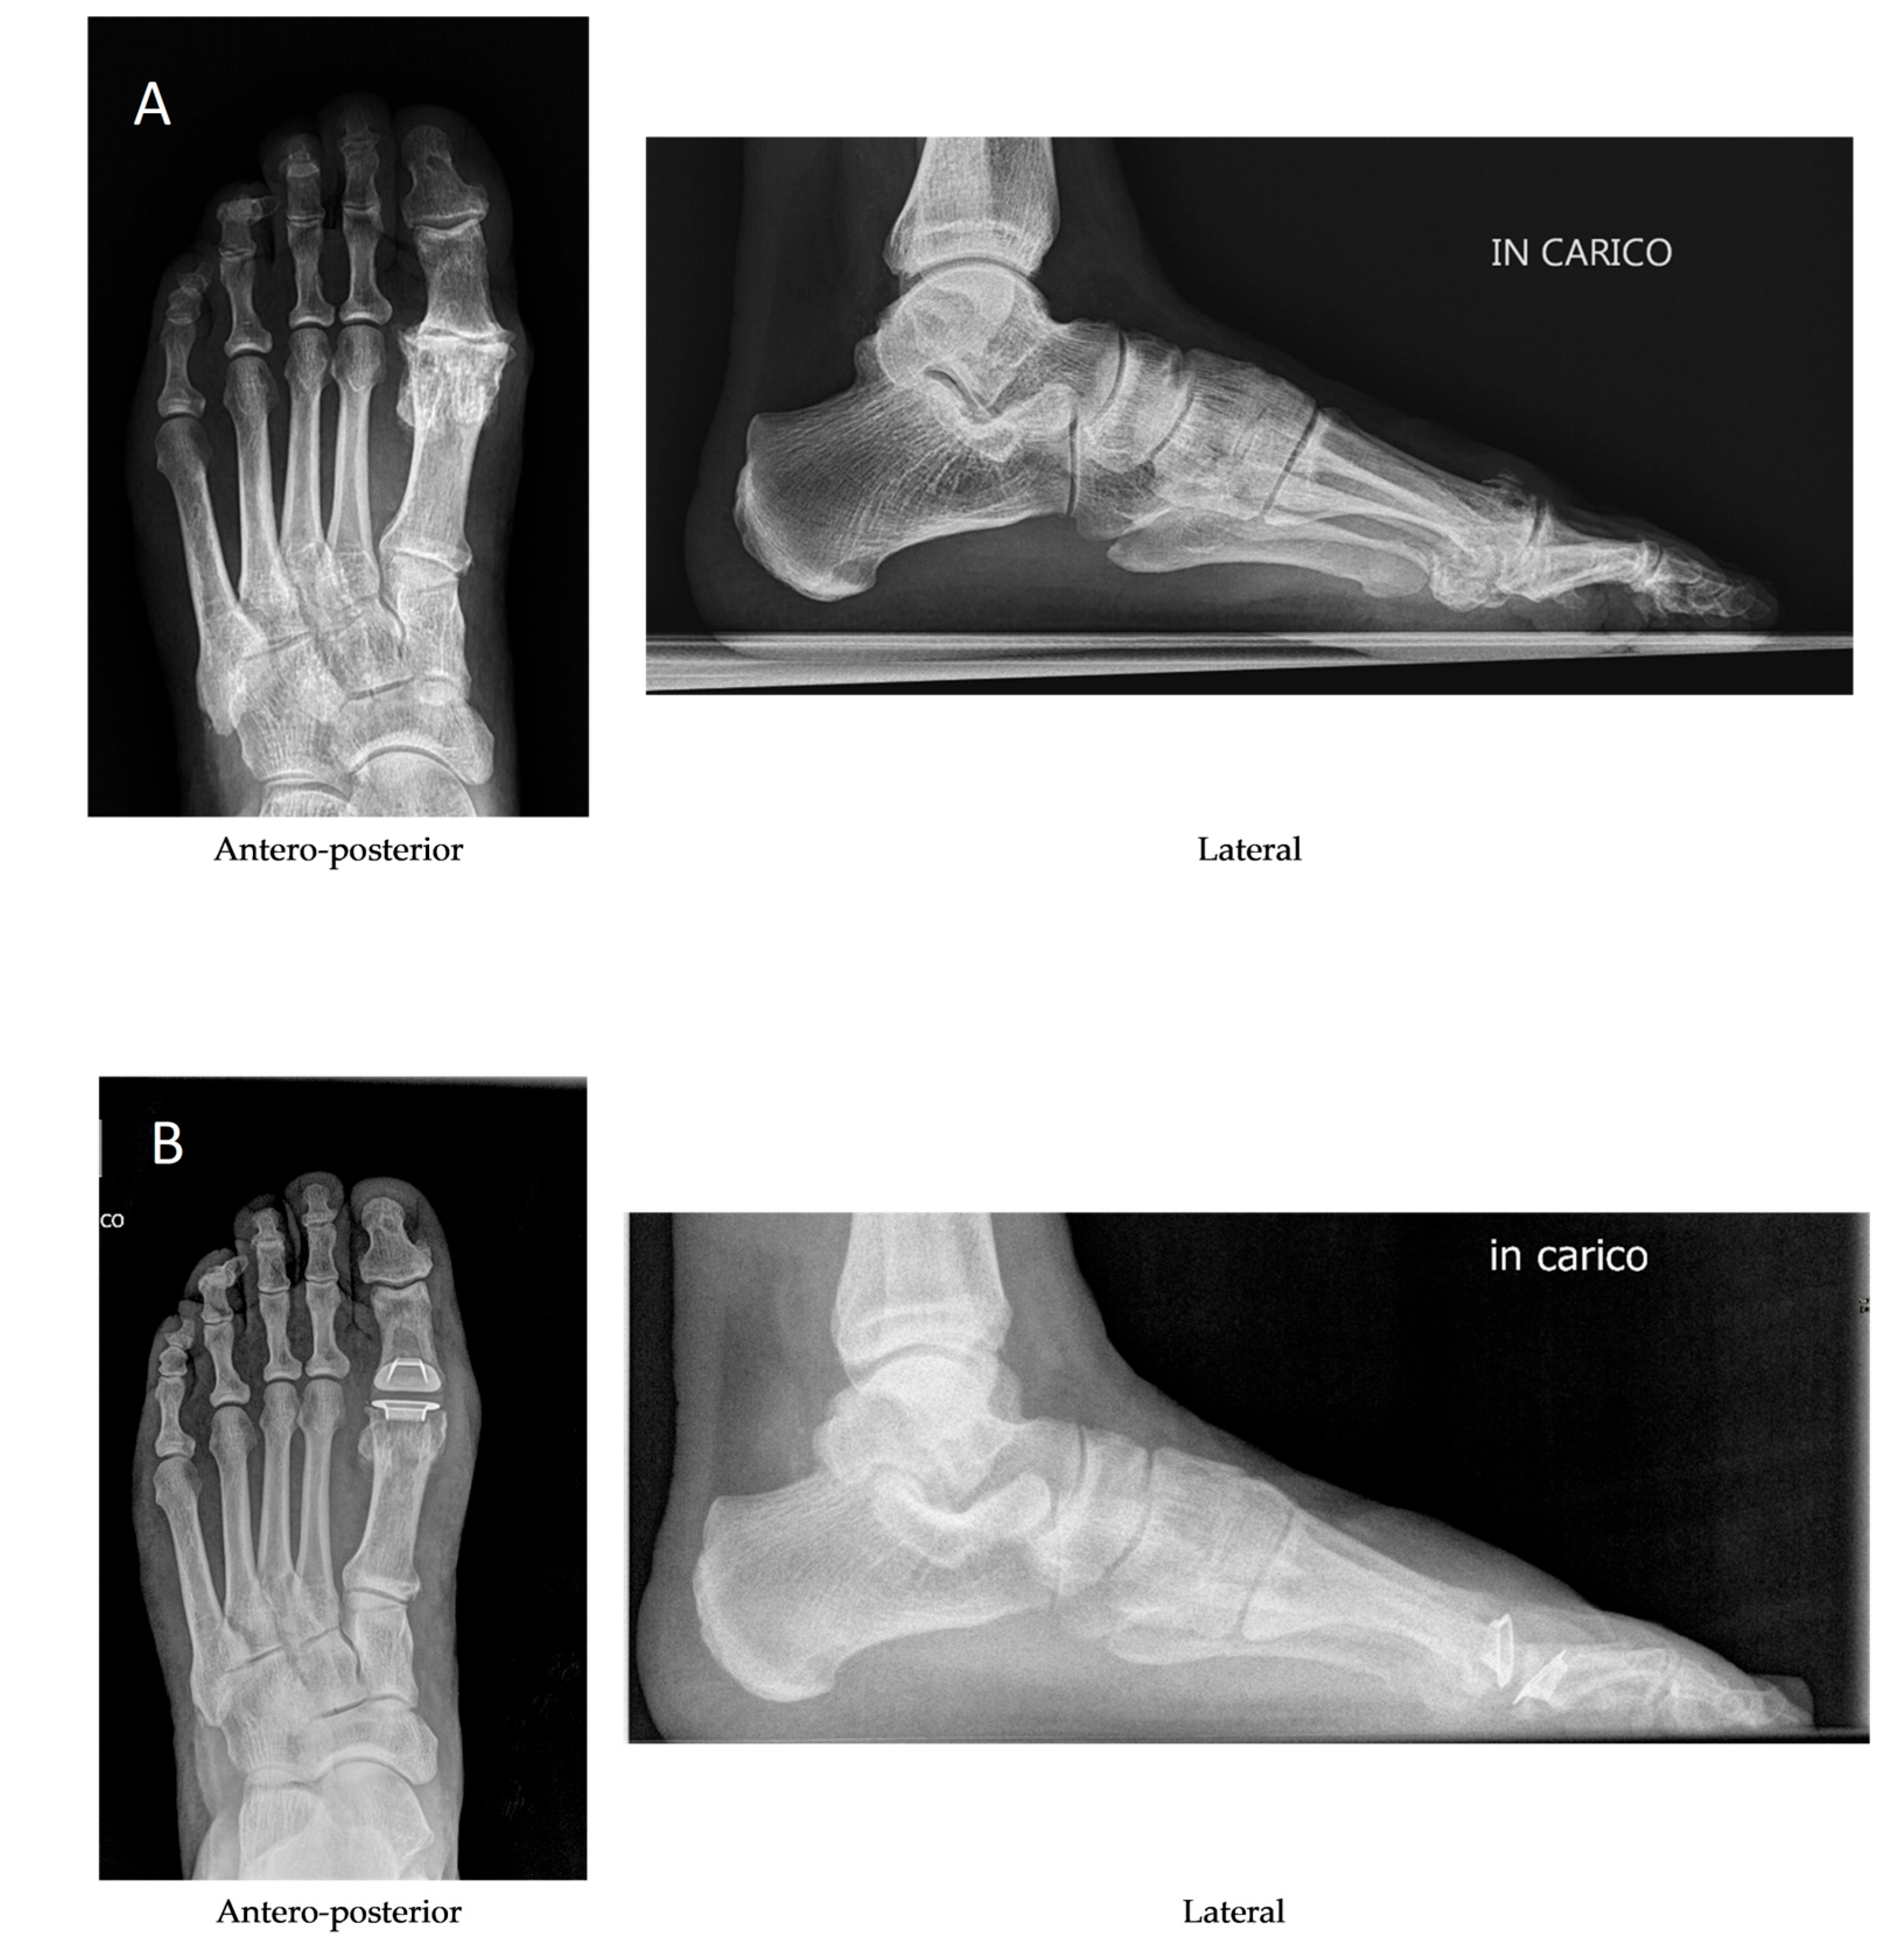

1. Introduction

2. Materials and Methods

2.2. Operative Technique, Postoperative Care and Follow-Up